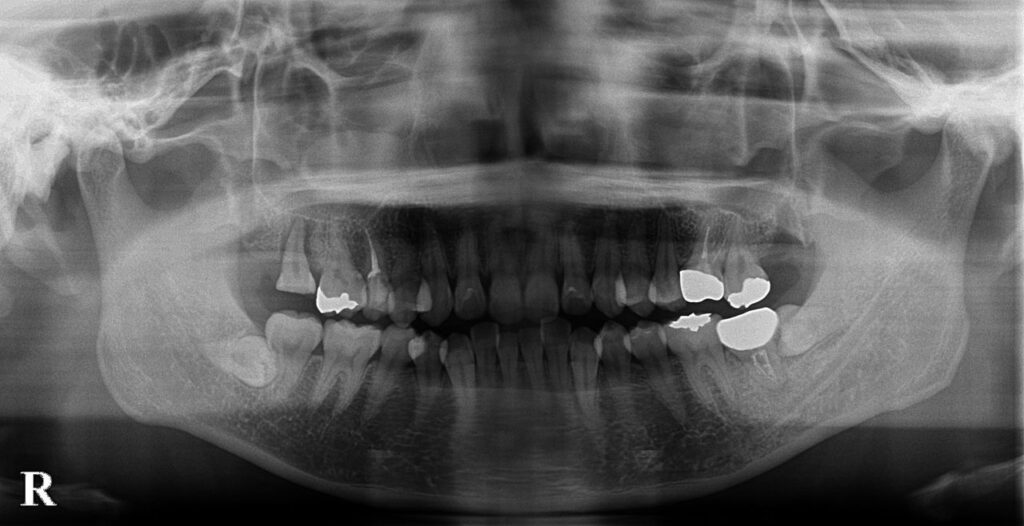

移植後のレントゲン写真です。